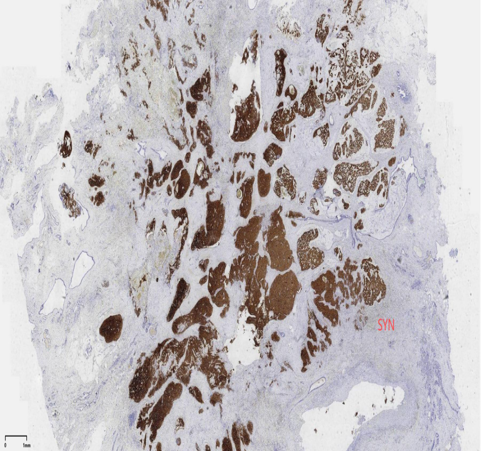

具有神经内分泌表达:CgA、Syn(约70%的比例,阳性细胞表达不等)

CK5/6、CKH-,可斑驳性的残留